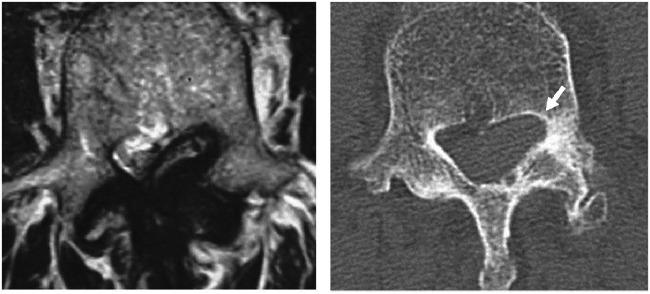

Spinal epidural hematoma (SEH) is an uncommon disorder, and chronic SEHs are rarer than acute SEHs. However, there is few reported involving the bone change of the vertebral body in chronic SEHs. We present a case report of lumbar epidural hematoma that required differentiation from extramedullary spinal tumors by a long process because the CT scan revealed scalloping of the vertebral body and review the relevant literature. A 78-year-old man had experienced a gradual onset of low back pain and excruciating pain in both legs. Lumbar MRI on T1-weighted images revealed a space-occupying lesion with a hyperintense signal relative to the spinal cord with no enhancement on gadolinium adminisration. Meanwhile, T2-weighted images revealed a heterogeneous intensity change, accompanying a central area of hyperintense signals with a hypointense peripheral border at the L4 vertebra. Moreover, the CT scan demonstrated scalloping of the posterior wall of the L4 vertebral body which is generally suspected as the CT finding of spainal tumor. During the epidural space exploration, we found a dark red-colored mass surrounded by a capsular layer, which was fibrous and adhered to the flavum and dura mater. Microscopic histological examination of the resected mass revealed a mixture of the relatively new hematoma and the hematoma that was moving into the connective tissue. Accordingly, the hematoma was diagnosed as chronic SEH. The particular MRI findings of chronic SEHs are helpful for making accurate preoperative diagnoses of this pathology.

脊髓硬膜外血肿(SEH)是一种罕见的疾病,慢性SEH比急性SEH更为少见。然而,很少有报道涉及慢性SEH中椎体的骨质改变。我们报告一例腰椎硬膜外血肿病例,因其CT扫描显示椎体呈扇贝样改变,病程较长,需要与髓外脊髓肿瘤相鉴别,并回顾相关文献。一名78岁男性逐渐出现腰痛和双下肢剧痛。腰椎MRI的T1加权像显示相对于脊髓有一个高信号占位性病变,注射钆后无强化。同时,T2加权像显示强度不均匀改变,L4椎体中央有高信号区,周边有低信号边界。此外,CT扫描显示L4椎体后壁呈扇贝样改变,这通常被怀疑是脊髓肿瘤的CT表现。在硬膜外腔探查过程中,我们发现一个暗红色肿块,周围有一层包膜,包膜为纤维性,附着于黄韧带和硬脑膜。对切除肿块进行显微镜组织学检查发现,肿块内既有相对较新的血肿,也有正在向结缔组织内蔓延的血肿。因此,该血肿被诊断为慢性SEH。慢性SEH的特殊MRI表现有助于对此病理情况做出准确的术前诊断。